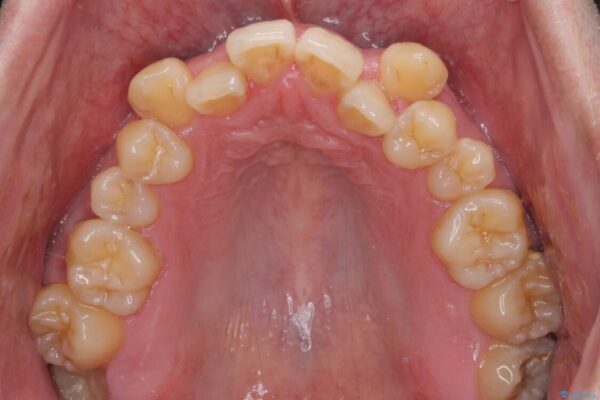

八重歯と前歯のクロスバイトを改善したいとのことで来院された患者様です。

デコボコの程度は強かったのですが、口元の突出感はなかったため、非抜歯矯正としました。

治療前

• 八重歯とクロスバイト 目立たないワイヤー装置で矯正治療 治療前画像